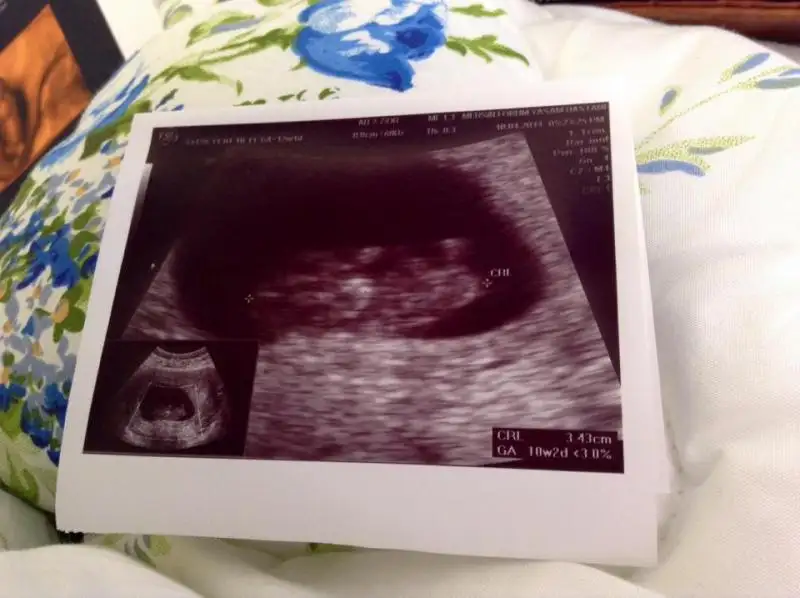

$100_0199.webp Burda 12. haftamızı bitiriyoruz doktoromuz cinsiyetini görmüs ama heyecanlı olması için haftaya söyleyecek.öğrenince yazarım.

cnm kac haftalik sanki buyuk duruyor

12+2 olduk bu gün teyzesi doktorumuz görmüs ama haftaya söyleyecekmis heyecanlı olsun diye :) ben ölüyorum meraktan haberi yok :))) siz tahminlerinizi yapın c.tesi kontrol sonucunu yazcam zaten.:emir_bebek: